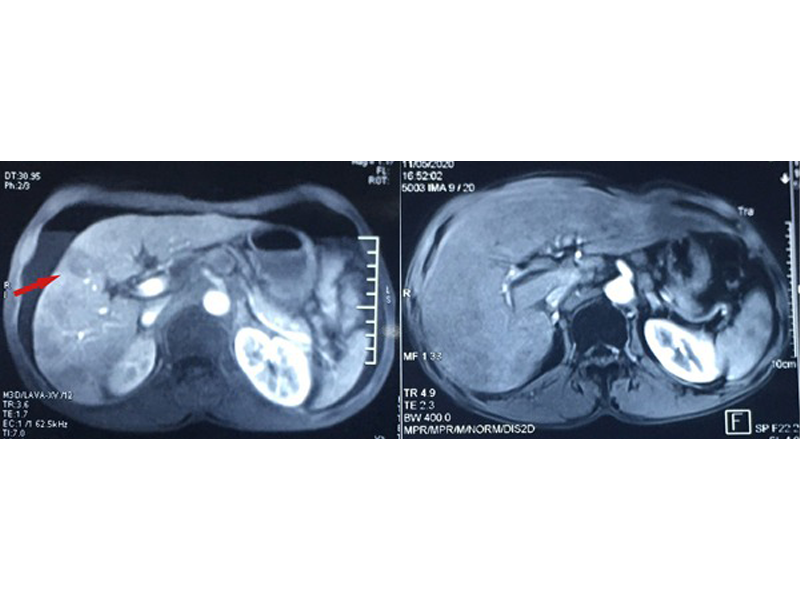

Hình ảnh các hạch di căn tại gan trước khi điều trị (trái) và hình ảnh sau truyền hoá chất 4 lần

Đặc biệt, ung thư đã di căn xuống gan với ổ lớn nhất đường kính 3 cm. Bác sĩ chẩn đoán bệnh nhân đã mắc ung thư giai đoạn muộn, các biện pháp phẫu thuật, điều trị tại chỗ không còn tác dụng nên chỉ định điều trị hoá chất toàn thân.

Sau chu kỳ đầu tiên, bệnh nhân đáp ứng thuốc tốt và đã có thể nuốt thức ăn. Kết thúc 4 lần truyền, bệnh nhân tiến triển rất khả quan, hiện bệnh nhân ăn tốt, tăng lên 50kg. Đáng mừng hơn là kết quả xét nghiệm không còn thấy tổn thương di căn gan, khối u ở thực quản cũng nhỏ lại.